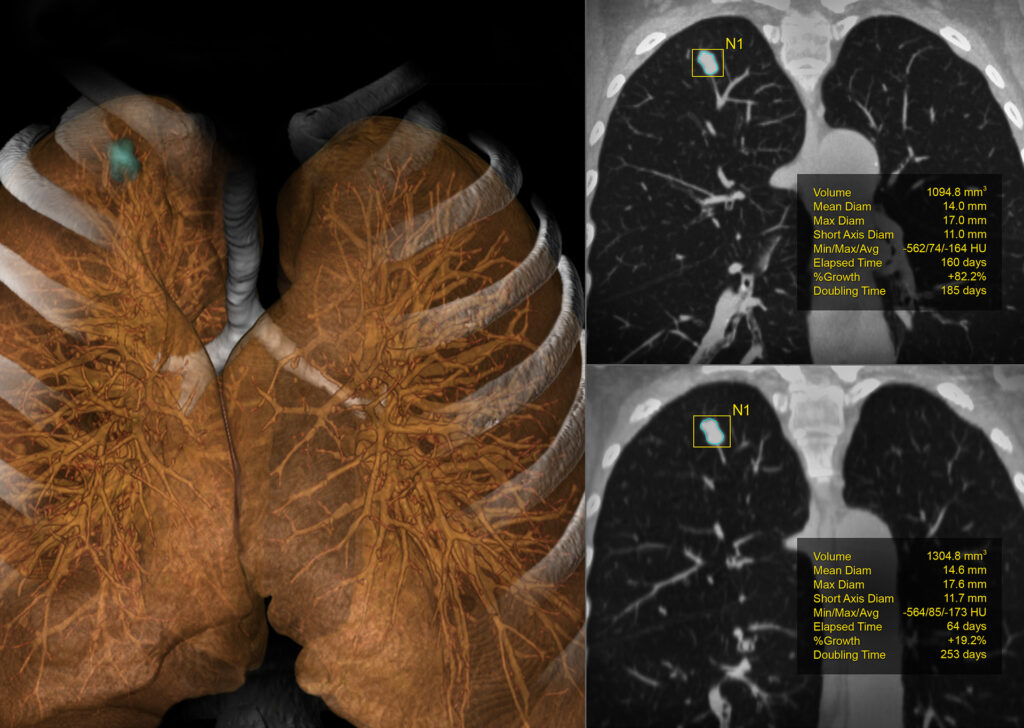

CT Lung Analysis

CT Lung Analysis aids in measuring and characterizing lung nodules. The interface and automated tools help to efficiently determine growth patterns and compose comparative reviews.

Visia™ CT Lung CAD

Visia CT Lung CAD is integrated into Vitrea® Advanced Visualization and facilitates time-efficient and safe radiological diagnosis of MSCT-images in clinical daily routine.